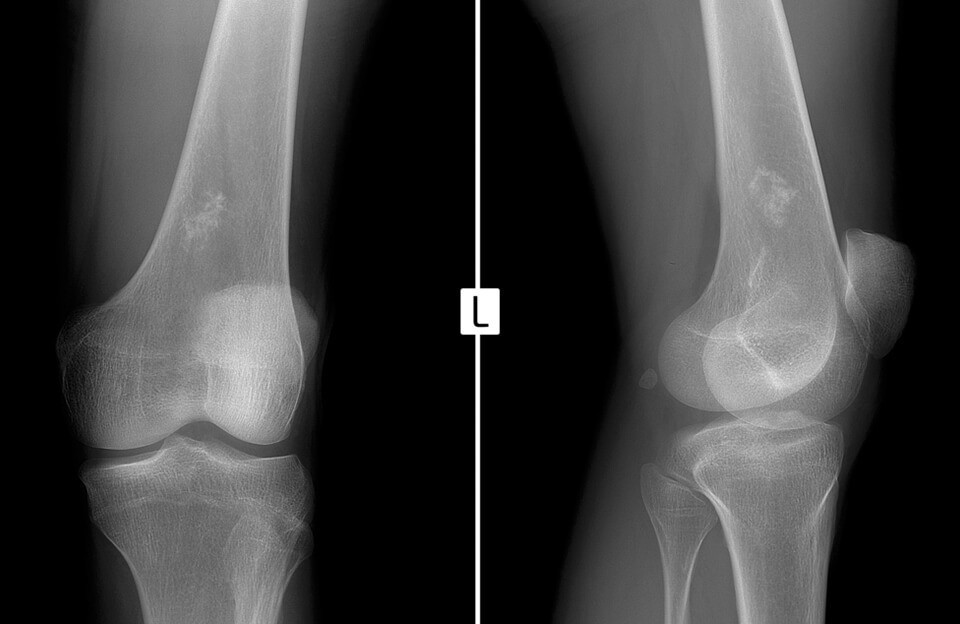

Первичный осмотр дополняется рентгенографическим исследованием кости, которое и показывает наличие опухоли (когда самой опухоли еще не видно, можно определить соседние участки кости, которые уже вовлечены в опухолевой процесс).

При костной саркоме рентген покажет нечеткие слои кортикальной пластинки костной массы, изменение мягких тканей. При этом очаги обызвествления и патологические хрящевые включения будут отсутствовать.

Базовым методом обнаружения саркомы Юинга является рентгенография: она дает возможность визуализировать опухоль, определить ее размеры и стадию развития. Особенности рентгенологической картины при исследовании костей, пораженных саркомой Юинга:

- комбинация остеосклеротического и деструктивного процессов костеобразования;

- расслоение, нечеткость контуров и разделение на волокна кортикального слоя;

- мелкие игольчатые и пластинчатые формирования в структуре надкостницы;

- изменение мягких тканей возле опухоли, которое зачастую превышает ее по размерам;

- отсутствие в мягкотканном компоненте хрящей, кальцинатов и элементов патологической костной ткани.

Кроме того, при обследовании пациента с подозрением на саркому Юинга используются такие инструментальные методы, как:

- компьютерная и магнитно-резонансная томографии – позволяют точно оценить размеры новообразования и его связь с нервно-сосудистым пучком, а также наличие метастазов;

- рентген и КТ легких – показывают вторичных раковые очаги;